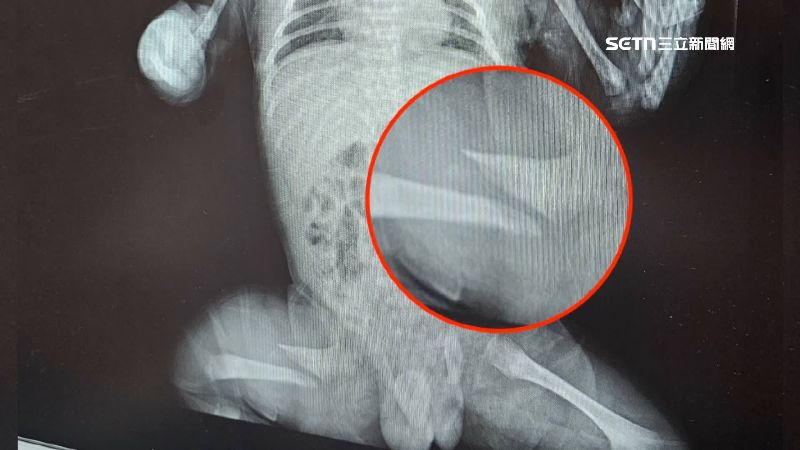

送醫後發現男嬰右大腿骨頭斷裂

送醫後發現男嬰右大腿骨頭斷裂。

送醫後男嬰右大腿骨頭竟然斷了,這讓好不容易求子成功的母親整天以淚洗面,而父親只能堅強起來替兒追真相。

這對新手爸媽怒控台中太平區產後護理之家涉及兒虐。去年底產婦與嬰兒入住,今年1月2日寶寶因為右腿骨斷裂持續哭鬧,過了兩日月子中心終於發現腿部腫脹有異,才通知家長。送醫後確定骨頭斷裂,由於嬰兒太小無法手術,只能打石膏固定、穿吊帶。